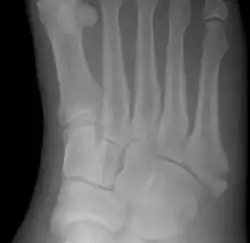

Pseudo-Jones fracture

Other proximal fifth metatarsal fractures exist, although they are not as problematic as a Jones fracture. If the fracture enters the intermetatarsal joint, it is a Jones fracture. If, however, it enters the tarsometatarsal joint, then it is likely an avulsion fracture caused by pull from the fibularis brevis tendon. An avulsion fracture at the base of the fifth metatarsal is sometimes called a "dancer's fracture" or a "pseudo Jones fracture", and usually responds readily to non-operative treatment.[18] The X-ray appearance of the developmental "apophysis" in this area may have some resemblance of a fracture, but is not a fracture; it is the secondary ossification center of the metatarsal bone. It is a normal finding that occurs at this site in adolescents.[19] If an injury to that area has occurred, the physician is often able to interpret certain radiographic clues to make the differentiation. An avulsion fracture at this location is typically extra-articular and oriented transversally as compared to the longitudinal orientation of an unfused apophysis.[19]